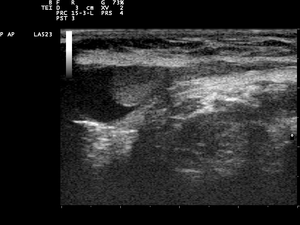

In the minority of cases with bilaterally non-palpable testes, further testing to locate the testes, assess their function, and exclude additional problems is often useful. Pelvic ultrasound or magnetic resonance imaging performed and interpreted by a radiologist can often, but not invariably, locate the testes while confirming absence of a uterus. A karyotype can confirm or exclude forms of dysgenetic primary hypogonadism, such as Klinefelter syndrome or mixed gonadal dysgenesis. Hormone levels (especially gonadotropins and AMH) can help confirm that there are hormonally functional testes worth attempting to rescue, as can stimulation with a few injections of human chorionic gonadotropin to elicit a rise of the testosterone level. Occasionally these tests reveal an unsuspected and more complicated intersex condition.

Inguinal cryptorchidism in a Chihuahua